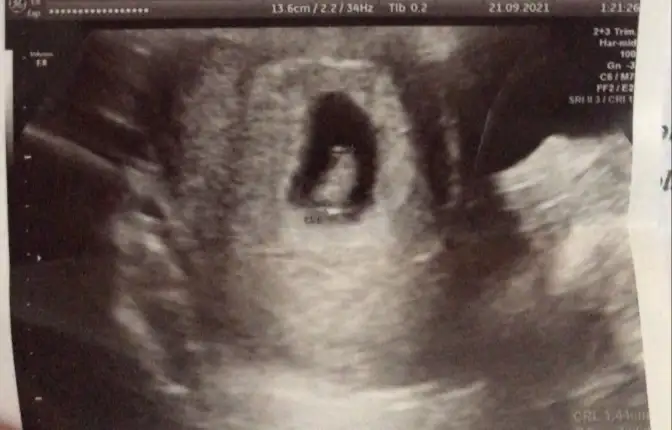

Bir de bacak arası fotosu var

Eklentiler

• Ekran Alıntısı.webp

Ekran Alıntısı.webp

8,8 KB · Görüntüleme: 158